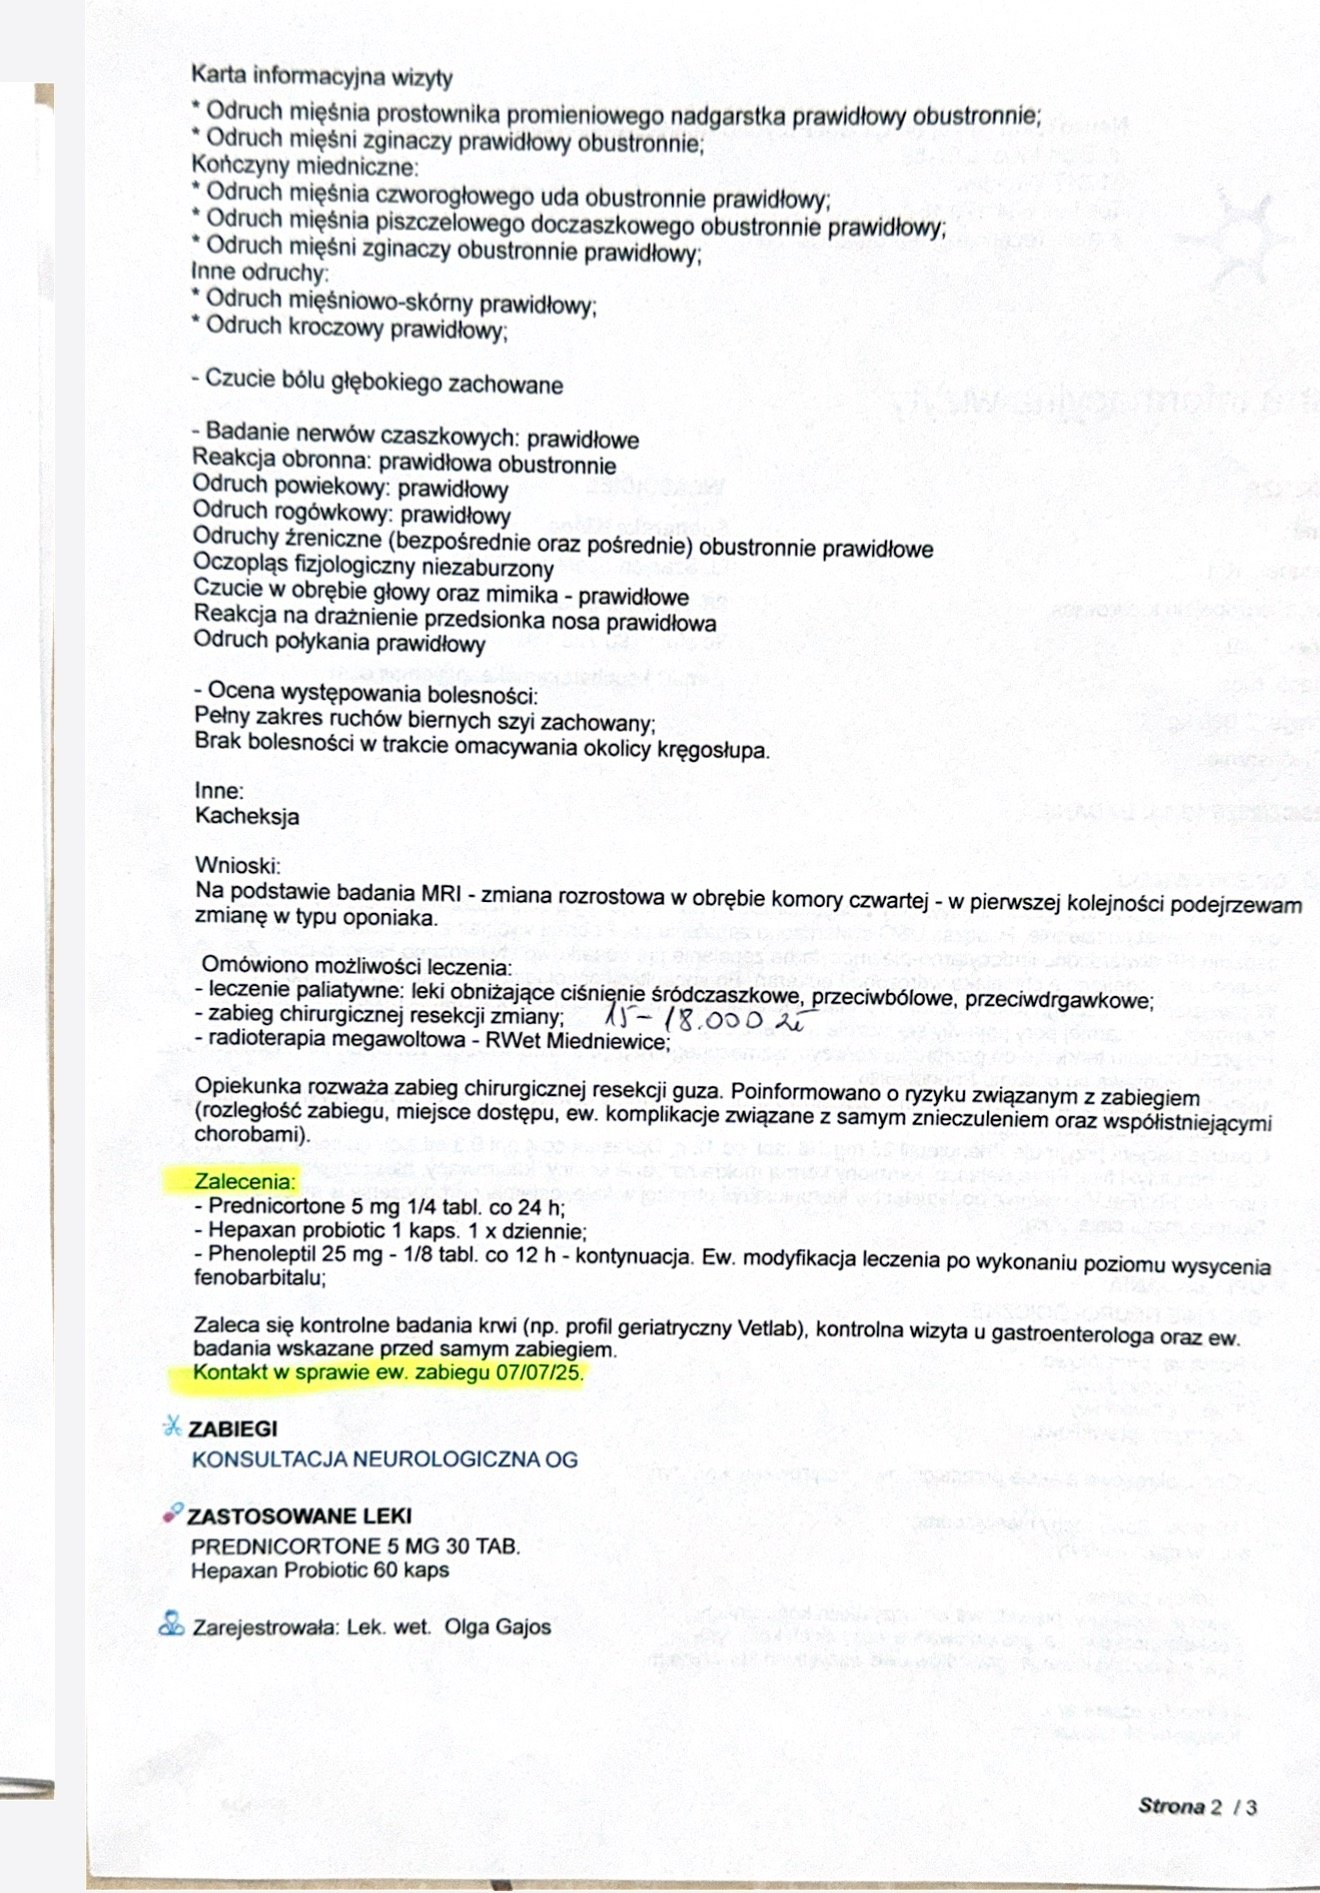

Cześć nazywam się Kinga Sucharska, jestem właścicielką już teraz 2 cudnych kotów. W styczniu 2025 pożegnałam swoją najstarszą kotkę, która zachorowała na nowotwór płaskonabłonkowy żuchwy. Dzisiaj zwracam się do Was z ogromną prośbą w imieniu mojego kotka 7 letniego Filusia o wsparcie finansowe i pomoc w jak najszybszym powrocie do normalnego funkcjonowania i szansy na dalsze życie. Po prawie 2 latach diagnostyki, leczenia w ciemno, czy doraźnej pomocy farmakologicznej otrzymaliśmy diagnozę w postaci nowotworu mózgu jakim jest OPONIAK. Na szczęście dostaliśmy szansę i możliwość na usunięcie guza w klinice NeuroTeam we Wrocławiu. Niestety Koszt takiej operacji wynosi od 15 do 18 tysięcy złotych. Pomijając koszty dalszego leczenia, dojazdów czy ewentualnej dalszej hospitalizacji kotka (cena za dobę w klinice to koszt 900zł). Niestety koszta tejże operacji przerastają Nas, tym bardziej, że jego wcześniejsze diagnozowanie wyniosło mnie już ogromną sumę.

16.06.25 wykonaliśmy rezonans w Poznaniu w klinice Wąsiatycz, który wykazał nam zmianę w postaci oponiaka, niestety bez pobrania płynu ze względu na jego duży nadmiar, a doktor wskazał to jako przeciwwskazanie do wykonania tego zabiegu.

23.06.25 Udaliśmy się z polecenia na wizytę konsultacyjną do kliniki NeuroTeam we Wrocławiu, gdzie dostaliśmy wstępnie zielone światło na wykonanie operacji. Tylko dzięki temu będziemy w stanie uratować mojego Filusia i dać mu szansę na dalsze życie z dala od bólu i cierpienia. Jest ze mną od miesięcznego malucha i nie wyobrażam sobie, aby choroba taka jak ta mi go zabrała, jest moim synkiem. Rokowania bez operacji są bardzo niskie, ze względu na jego dotychczasowe samopoczucie, utrzymujące się wymioty (rzadziej ale jednak nadal występują - w postaci samej wody lub śliny), wagę (2kg) oraz jelita, które słabo pracują pomimo codziennych leków.

Aktualne leki, które otrzymuje to steryd prednicortone, gasprid, ursopol, phenoleptil, rzadziej przeciwwymiotne oraz stale probiotyk

07.07.25 czekamy na telefon od doktora Wrzoska w sprawie dokładnego omówienia naszego przypadku oraz ustalenia terminu operacji.